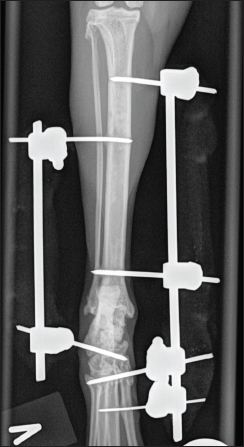

Fig. 2. (A and B) Mediolateral and craniocaudal digital radiograph of the left hock joint eight weeks post-operative. The fracture line was well visible. The lateral frame was removed at this stage.

Eight weeks postoperatively, the cat was back for re-examination and radiographs. The owner reported that the cat moved freely around the house after 6 weeks of cage rest. The cat was anesthetized as previously, orthogonal radiographs revealed good fracture healing (Fig. 2a and 2b), and the lateral frame was removed according to standard procedures (Kraus et al., 2003). Twelve weeks postoperatively, the cat was back for re-examination and radiographs, and the owner could report that the cat was doing fine. The cat was anesthetized as previously for orthogonal radiographs, which revealed good fracture healing, and the medial frame was removed. A set of new orthogonal radiographs was taken after frame removal. Palpation of the affected talocrural joint revealed a moderately reduced range of motion (ROM) compared to the opposite joint. Measurements with a goniometer showed left extension at 160°, flexion at 67°, right extension at 167°, and flexion at 20° (Jaeger et al., 2007). Thirty-three weeks postoperatively, the cat was seen for a progress check. The cat was still not allowed outdoors. Slight lameness was evident when the cat moved freely on the floor. There was no pain or swelling in the affected area during palpation, and the ROM had improved, but it was still reduced compared to the opposite limb (left extension 163° and flexion 30°). The cat was anesthetized as previously for orthogonal radiographs (Fig. 3a and 3b).